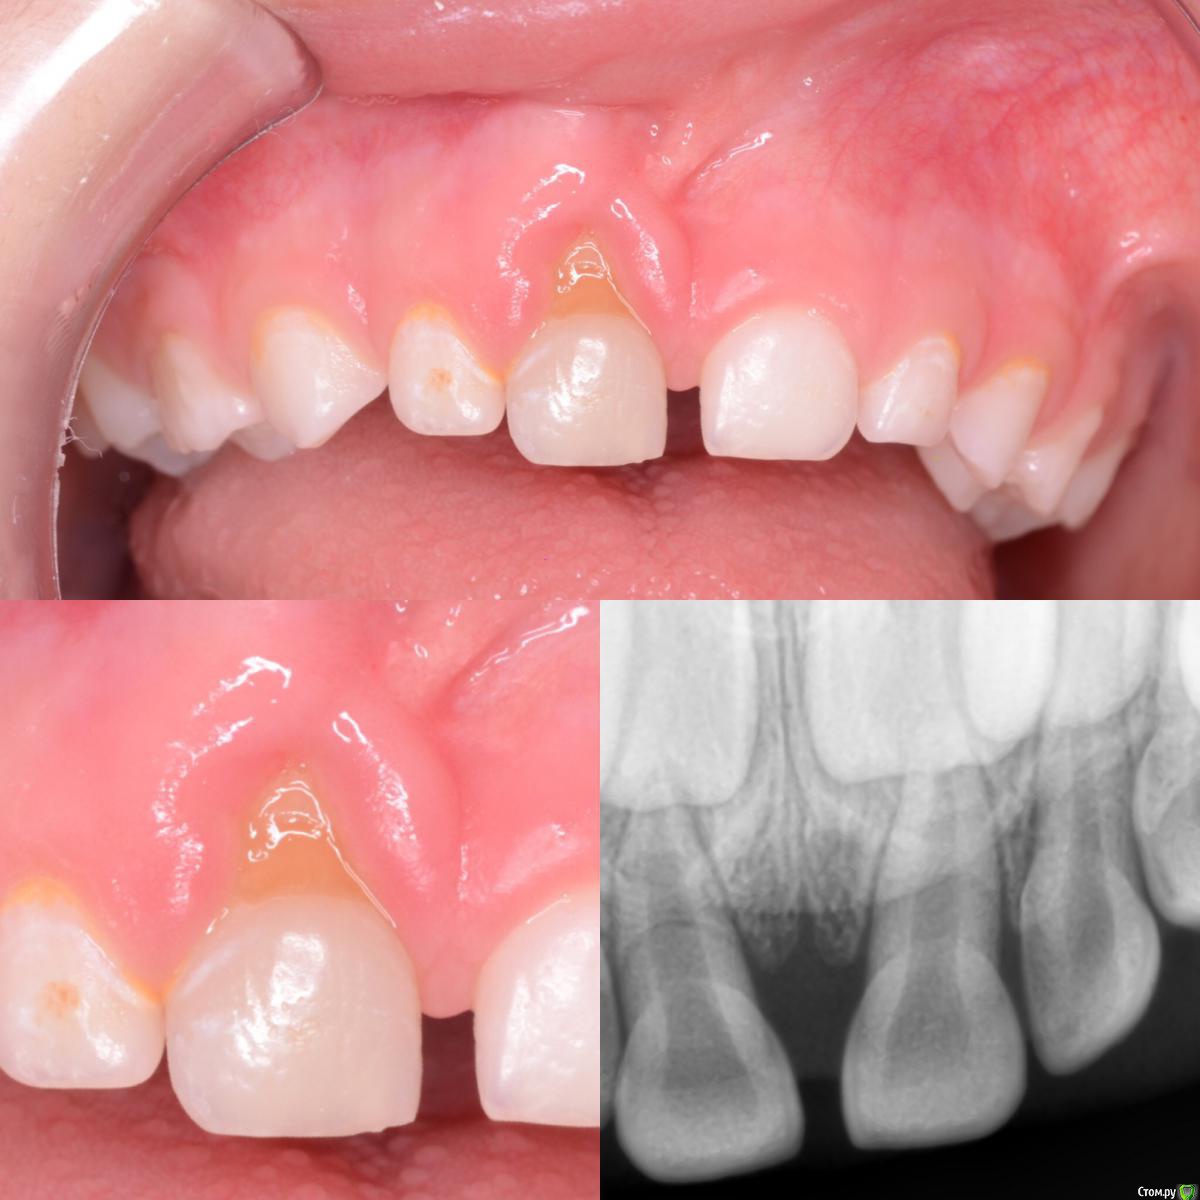

CRAZYDUCK Опубликовано 16 мая, 2018 Автор Поделиться Опубликовано 16 мая, 2018 Про травму можно много написать . Главное , пожалуй , осмотр и снимок травмированных зубов в день осмотра ( проверяем мягкие ткани на предмет инородных тел - осколки зубов, частички земли, модно сделать RVG мягких тканей , чтобы ничего не пропустить ). Есть такой термин «асфальтовая татуировка»- остаются частички асфальта или ещё чего в травмированных мягких тканях . RVG зуба через неделю - может увидеть перелом корня без смещения , обломки будут разъединены на снимке сгустком крови ( этого на первом снимке может не быть). Далее снимки каждые 3-4 месяца в течение 9-12 месяцев. Можем наблюдать бессимптомную гибель пульпы . Изменение цвета коронковой части само по себе не является показанием к экстирпации , если снимок «хороший». 1 1 Ссылка на комментарий

CRAZYDUCK Опубликовано 16 мая, 2018 Автор Поделиться Опубликовано 16 мая, 2018 (изменено) Катя 3,8 лет, травма 5.1 была в январе 2017 ( я увидела впервые Катю два дня назад ). 5.1 не подвижен !!!( в пределах нормы физиологической подвижность ). На фото выглядит так будто он держится на «честном слове», патологии на RVG тоже нет . Изменение цвета есть . Наблюдаем .книжка по травме хорошая . Изменено 16 мая, 2018 пользователем CRAZYDUCK 3 Ссылка на комментарий